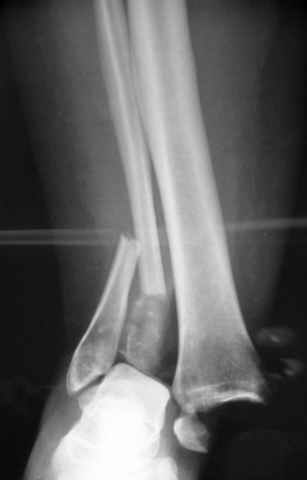

Второй случай сделан из одного разреза

На прямой проекции послеоперационного Рг макроскопически все выглядит очень анатомично, при микроскопическом ( :-)) ) рассмотрении можно все-таки заметить вальгизацию тарана, суставная щель в латеральном отделе сустава несколько уже , чем в медиальном при отсутствии латерального смещения тарана. У меня был аналогичный случай (без LISS , без мини доступа) с вальгусным наклоном тарана при восстановленном ankle mortise при последовательном наблюдении с интервалами в 6-8 недель в послеоперационном периоде отмечалось прогрессирующее сужение суставной щели в латеральном отделе сустава, закончившееся посттравматическим ОА, к счастью боли умеренные, купируемые аналгетиками или своими эндорфинами:-))(активная пациентка, у которой нет времени на болезни....) Какова жизненная ситуация в приведенном вами случае? И последнее, что я хотел бы прояснить для себя - фиксация внутренней лодыжки: я обычно комбинирую фиксацию компрессирующим винтом со спицей - по идее ротационная стабильность должна быть лучше, чем один винт, каковы ваши наблюдения в этом плане?